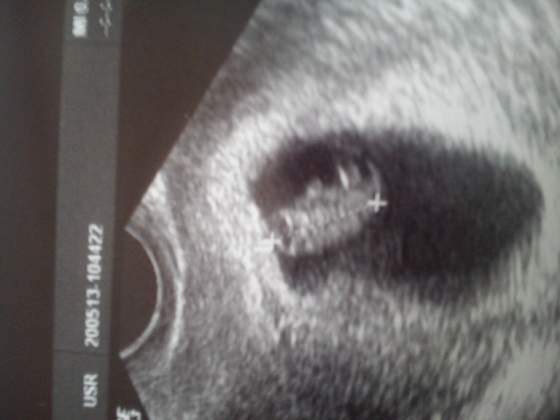

15,6 mm :D z USG dokładnie 8 tygodni 0 dni :D serce bije jak dzwon :) Jaka ja jestem szczęśliwa!!!!

Zaraz jak się uspokoję to więcej napiszę :D

Fasolka 2.jpg

Nie wiem czemu takie przewrócone jest.... nie umiem normalnie wkleić...